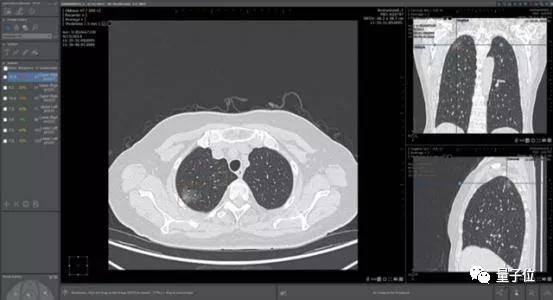

除了之前提到的临床应用Streams,他们还开发了可以筛查乳腺癌和识别50多种眼疾的技术。

除了饱受争议的Streams应用,谷歌健康成立后重点宣传的糖尿病视网膜病变筛查业务,也在落地上出现了不少问题。

据谷歌发表在《美国医学会期刊》(JAMA)上的研究显示,AI算法在这一研究中起到的作用极大,使得这一工具的准确率达到了90%,理论上几秒就能出结果,“足以和眼科专家的诊断结果相媲美”。

医疗影像辅助诊断是当时医疗AI公司扎堆投入的领域。这家公司最大的卖点肺结节诊断,则是红海中的红海。

一家医院接入4、5家AI肺结节诊断产品成了司空见惯,曾有影像医师笑称:

中国人的肺结节都不够用了。